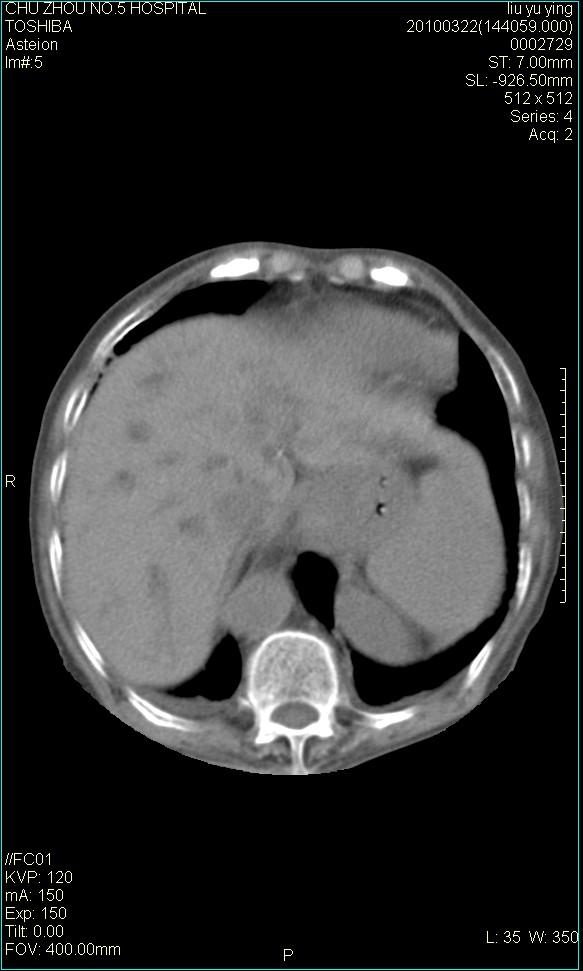

以下是引用科室第一人在2010-3-23 6:50:00的发言:[br]胆总管下段梗阻,多为肿瘤性病变,巨形胆囊,胆囊炎胆囊窝积液。[br]双侧胸腔积液,右降

以下是引用随光逐影在2010-3-23 8:12:00的发言:[br]1)胆系低位梗阻(肝内外胆管扩张,胆囊增大),原因待查。2)胆囊炎。3)双侧少量胸腔积液。4)降主动脉迂曲。